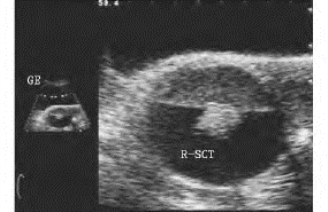

1.38.12十二、胎儿畸形